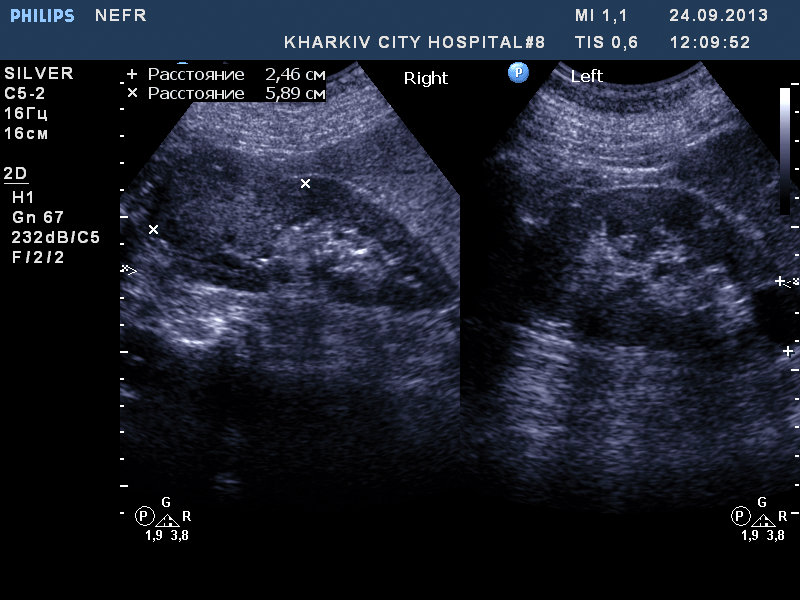

Пациентка 76 лет. Образование правой почки. Вероятно ПКР. Рекомендовал КТ и консультацию уролога.

Согласен.